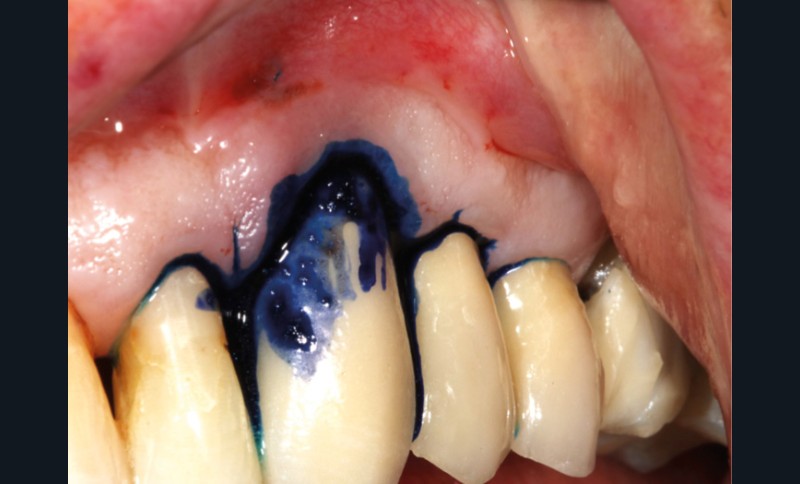

– thérapie photodynamique (bactéricide avec colorant photosensible) pour les lasers de faible énergie (600 à 800 nm),